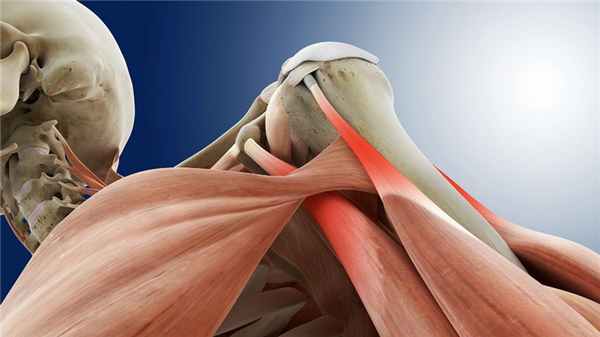

Повреждение вращательной / ротаторной манжеты плеча

ЧТО ТАКОЕ ВРАЩАТЕЛЬНАЯ (РОТАТОРНАЯ) МАНЖЕТА ПЛЕЧА И ДЛЯ ЧЕГО ОНА НУЖНА?

Вращательная (ротаторная) манжета плеча — включает надостную, подостную, малую круглую и подлопаточную мышцы. Эти мышцы необходимы для стабилизации головки плечевой кости и предотвращения ее смещения при движении в суставе. Кроме того, эти мышцы позволяют осуществлять вращательные движения в плече во всех направлениях.

Подлопаточная мышца вращает руку внутрь, надостная - поднимает плечо и "приякоривает" его, т.е. вжимает головку плечевой кости в суставную впадину лопатки при отведении плеча вбок. При этом основная сила отведения определяется дельтовидной мышцей, а надостная мышца работает как командир, направляющий усилия дельтовидной мышцы. Подостная мышца вращает плечо наружу, а малая круглая - вращает наружу и приводит руку к туловищу. Повреждение хотя бы одной из четырех мышц приводит к резкому ограничению движений и утрате функции плечевого сустава.